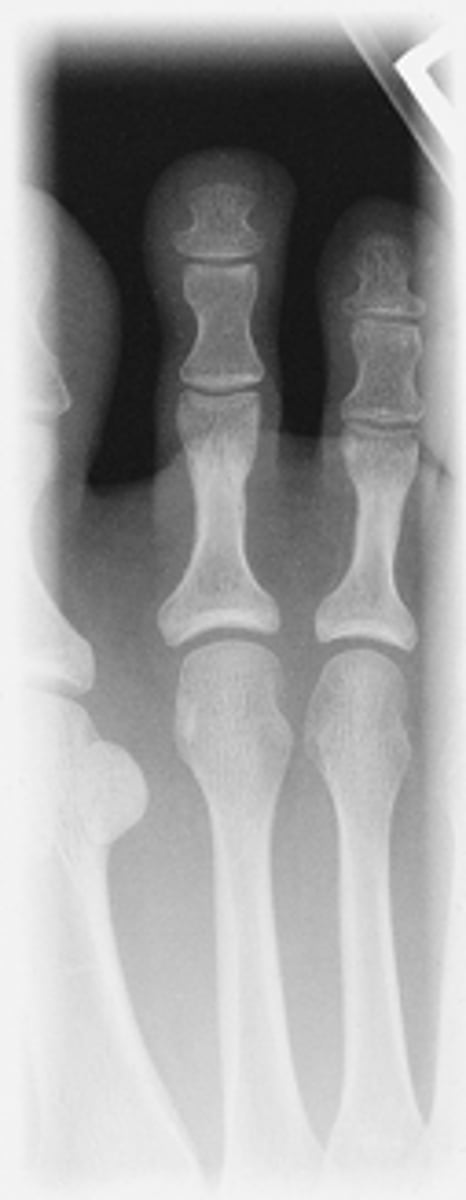

AP Second Digit

What projection is this?

Evaluation Criteria AP Toes Digit

- 15° wedge, CR perpendicular to IR

- Digits and minimum of distal ½ of metatarsal demonstrated

- No overlap of soft tissues

- IP and MTP joints appear open

- Optimal exposure factors